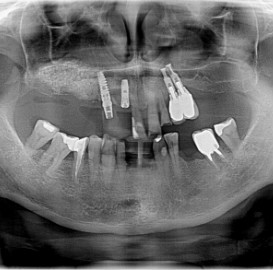

Lat 50, pół roku przed rozpoczęciem leczenia implantologicznego przestał palić papierosy. Znacząca poprawa higieny, pacjent silnie zmotywowany. Po regeneracji kości i rekonstrukcji tkanek miękkich odbudowa sześciu zębów na koronach porcelanowych. Na zdjęciu widoczna ilość i jakość tkanki kostnej po rekonstrukcji. W porównaniu ze stanem początkowym uzyskano znaczącą poprawę warunków kostnych nie do osiągnięcia metodami sterowanej regeneracji kości z użyciem reklamowanych markowych błon kolagenowych i dosypaniem kości z butelki.

Implantacja natychmiastowa. Zęby paradontyczne. Usuniete zgodnie z popularną obecnie na zachodzie techniką: usuń zęby zanim zaniknie kość. Wynikiem takiego postępowania jest mniejsza trauma dla pacjenta i krótszy okres trwania rehabilitacji protetycznej, niższe całkowite koszty leczenia. Ale jednocześnie więcej implantów i mniej własnych zębów. W długotrwałym okresie obserwacji takie podejście daje dobre wyniki.

Pacjent z długą historią leczenia implantologicznego. Pierwsze implanty w pozycjach 23, 24 miał wkręcane w Warszawie przed 25 laty. Implant w pozycji górnego prawego kła ma agresywny gwint, ponieważ bezpośrednio po implantacji był obciążony (immediate loading) tymczasowym atachmentem ball abutmentv do stabilizacji tymczasowej protezy ruchomej. Kość szczęki regenerowana i odbudowywana etapami w całym górnym prawym kwadrancie. Pacjent planuje uzupełnić brakujące zęby 25, 26.

Lat 38, Pacjent paradontyczny, obciążony genetycznie, niepalący, dobra higiena. Pionowa i pozioma regeneracja kości.

Pacjentka lat 72, od kilkudziesięciu lat chorująca na cukrzyce I typu, obecnie od 10 lat na pompie insulinowej. Profesor medycyny, siostrzenica pacjentki prowadzi swoją ciocię diabetologicznie, pacjentka świadoma zagrożeń przy zabiegach regeneracji kości i implantacji w takim ogólnym stanie zdrowia. Po rekonstrukcji tkanek miękkich i kości osadzono dwa implanty o średnicy 5,0 mm. Na zdjęciu śródzabiegowym widać zadowalające wyniki rekonstrukcji tkanki kostnej. Po upływie kilku miesięcy wykonano nadbudowę protetyczną.

Pacjentka po ekstrakcji kilku zębów, z implantacją natychmiastową, odroczoną. Zdjęcie pantomograficzne wykonano pięć lat po implantacji. Widoczna stabilna sytuacja kostna i dziąsłowa.